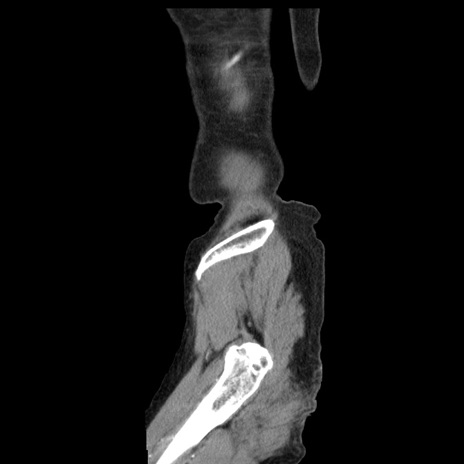

症例1(矢状断像)

【症例】80歳代女性

【主訴】腹痛

【現病歴】8時間前から腹痛あり来院。

【既往歴】糖尿病、脂質異常症、子宮体癌にて子宮全摘術

【身体所見】意識清明・会話良好だが腹痛で苦悶様、全腹部にわたって反跳痛と圧痛あり

【データ】WBC 13600、CRP 0.14、LDH 224、CK 90